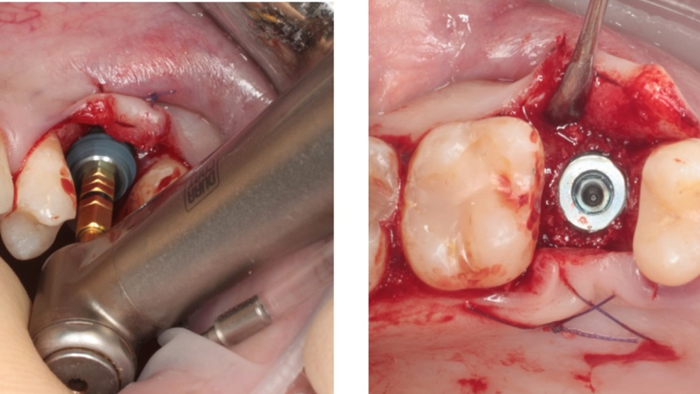

Clinical case: Ridge splitting technique using SmarThor + AnyRidge as expander

- Courtesy of Dr.Kwang-Bum Park, Korea -

Keywords

AnyRidge, ridge splitting, GBR, Dr. Kwang-Bum Park, mandibular posterior, SmartThor, Mega-Oss, thin ridge, bone regeneration

Products:

AnyRidge implant system. SmarThor, Mega-Oss